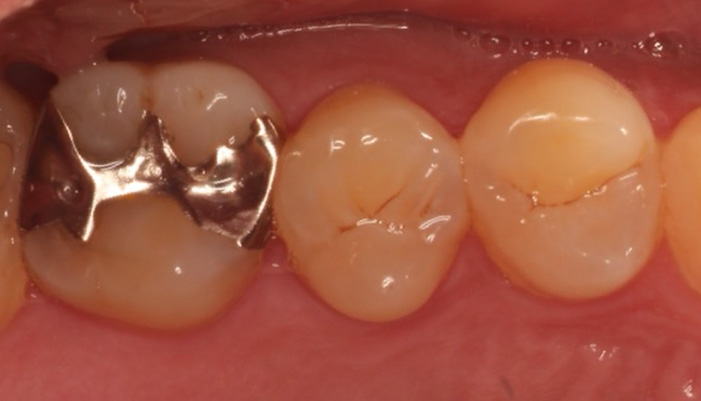

症例1

治療前

治療の経緯

患者様は「他院で神経を取るしかないと言われたが、できれば神経を残したい」とのご希望で来院されました。初診時には冷たいものがしみる症状はありましたが、自発痛や打診痛はなく、診査の結果、歯髄を温存できる可能性があると判断しました。

治療では拡大視野下でむし歯の感染部分を正確に除去し、MTAを用いた歯髄温存療法を実施しました。

| 主訴 | 歯に穴が空いた |

|---|---|

| 治療期間 | 1ヶ月 |

| 治療費 | ¥33,000 |

| 治療内容 | むし歯が大きく、神経を残す治療(歯髄温存療法)を行い、神経を残しダイレクトボンディングにて修復しました。 |

| 治療のリスク | 治療後に痛みが出ることがあります。また、痛みが強くでる場合は神経を取る治療に移行することもあります。 |